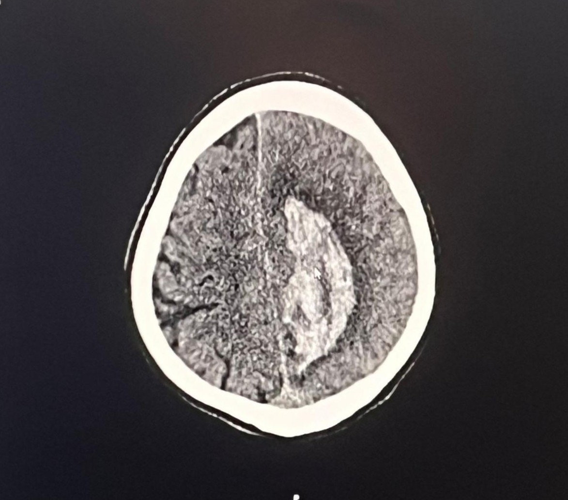

She was diagnosed with brain arteriovenous malformation last year. (Alicja Faryniarz via SWNS)

Alicja had a three inch AVM which ruptured and paralyzed the right side of her body and also left her in a coma for three days.

Alicja Faryniarz's brain scan. (Alicja Faryniarz via SWNS)